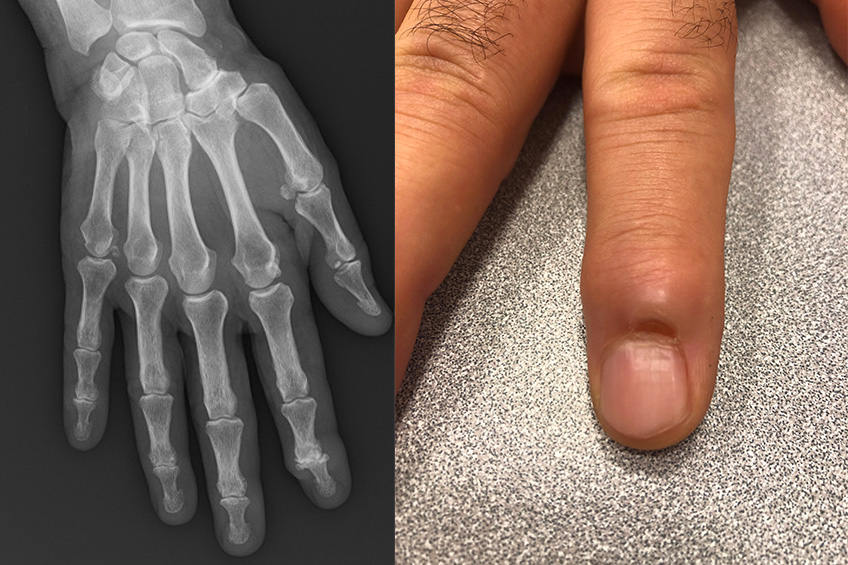

L’arthrose peut concerner toutes les articulations, y compris les interphalangiennes proximales (IPP) ou distales (IPD). La plus fréquente concerne les IPD.

Cette arthrose se manifeste par plusieurs signes qui peuvent être associés :

• un gonflement de l’articulation : il s’accompagne de douleurs, plus ou moins violentes. Il est important de préciser que l’arthrose peut être douloureuse par « crises »,

• une déformation latérale et dorsale de l’articulation,

• une désaxation de l’articulation,

• une diminution de la mobilité ou raideur,

• un pseudo-kyste dit « mucoïde ».